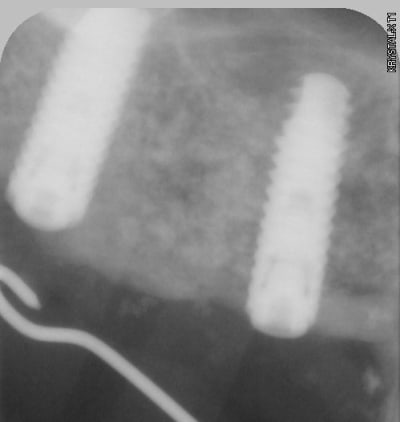

pour illustrer cette utilisation du bioactys, voici un cas (ce matin, mise en focntion des implants à 7 mois post_op)

ici c'est un mix (pour un impératif perso): en 25 un easy-implant master s puis 2 dentium superline.

j'ai donc procédé à la mise en fonction ce matin, 7 mois après l'intervention. Mise en place de piliers de cicatrisation assez hautes et surtout de diamètres en adéquation avec une PM et 2M. je prends l'empreinte dans 3 semaines , la gencive sera belle autour des piliers.